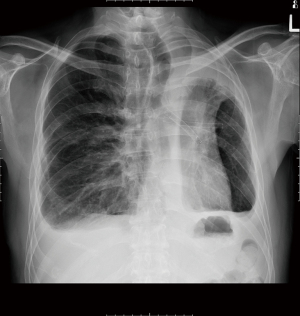

A 56-year-old male had a left thoracotomy and upper lobectomy in childhood for post-tuberculous hemoptysis. He presented now with recurrent infections from right lower lobe bronchiectasis for 3 years which was initially treated by medical therapy (Figure 5). As the bronchiectasis was limited to one lobe, he was referred for right lower lobectomy and decision was made to do by VATS. Initial intraoperative attempt to isolate right lung by standard left-sided double lumen tube failed due to inability of the left residual lobe to support adequate ventilation and oxygenation. The previously described technique of selective lobar selective lobar isolation technique was used to obtain selective right lung isolation. A right VATS lower lobectomy was performed uneventfully without resorting to thoracotomy (Video 3). Post-operative recovery was uneventful and he was discharged well on 4th post-operative day. He has remained well and asymptomatic 13 years after surgery and has been discharged from further follow-up.